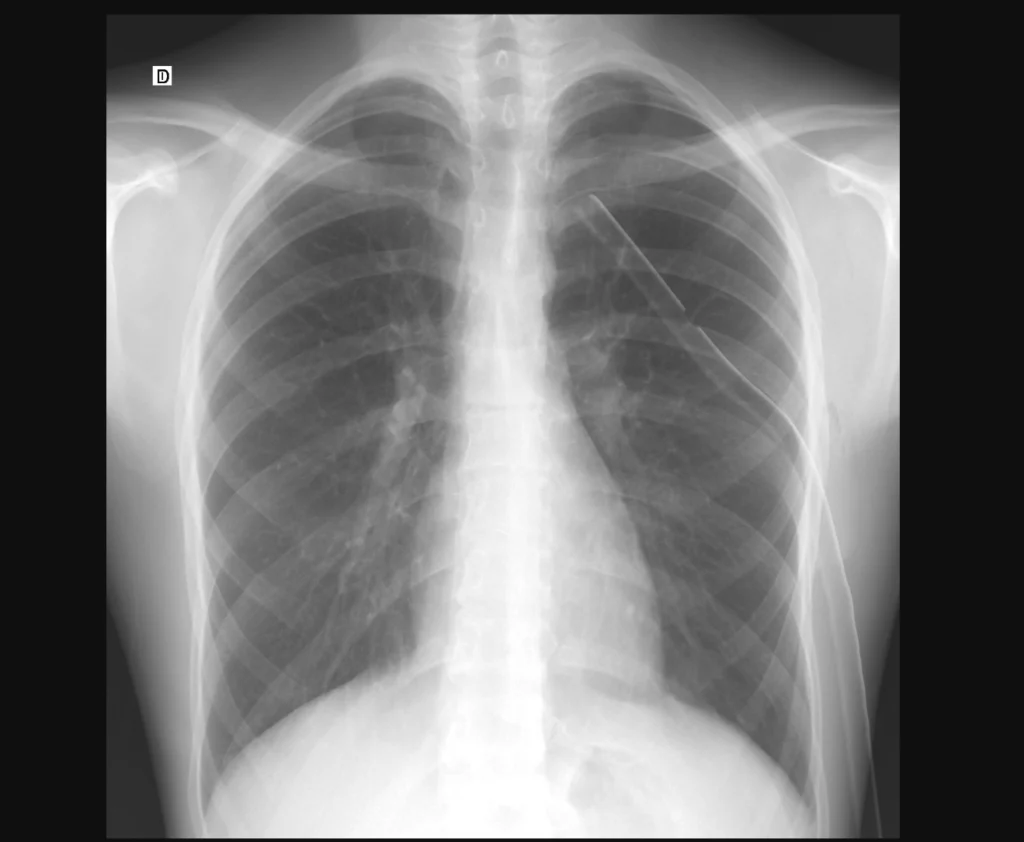

Rx de tórax PA post-tratamiento. Se colocó un tubo de drenaje en la cavidad pleural.